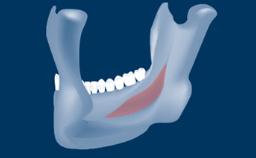

In this short microlearning module on digitally guided sinus floor elevation, we delve into a specialized aspect of the digital workflow for implant-guided surgery, focusing on the use of digital guides in the sinus floor elevation technique.

• understand the rationale and advantages of utilizing digital guides for sinus floor elevation (SFE)

• describe the indications for digital guides in SFE